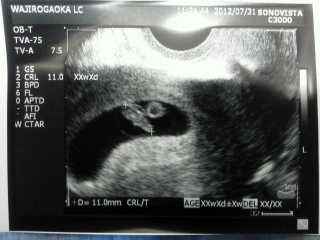

胎芽11.0mm。まだモヤモヤしてるけど

次は手や足とかわかるのかなー??楽しみ★

5週目の初診では見えなかった胎芽、2週間の間に11.0mmまで成長していて、ビックリだったけど、心拍も確認できて一安心です。

次回はお盆に入るので、8週目の終わり頃の検診予定です。